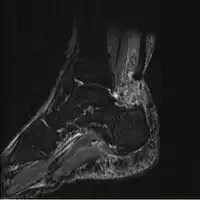

MRI can be used to discern incomplete ruptures from degeneration of the Achilles tendon, and MRI can also distinguish between paratenonitis, tendinosis, and bursitis. This technique uses a strong uniform magnetic field to align millions of protons running through the body. These protons are then bombarded with radio waves that knock some of them out of alignment. When these protons return they emit their own unique radio waves that can be analysed by a computer in 3D to create sharp cross sectional image of the area of interest. MRI can provide unparalleled contrast in soft tissue for an extremely high quality photograph making it easy for technicians to spot tears and other injuries.

Achilles tendon rupture -